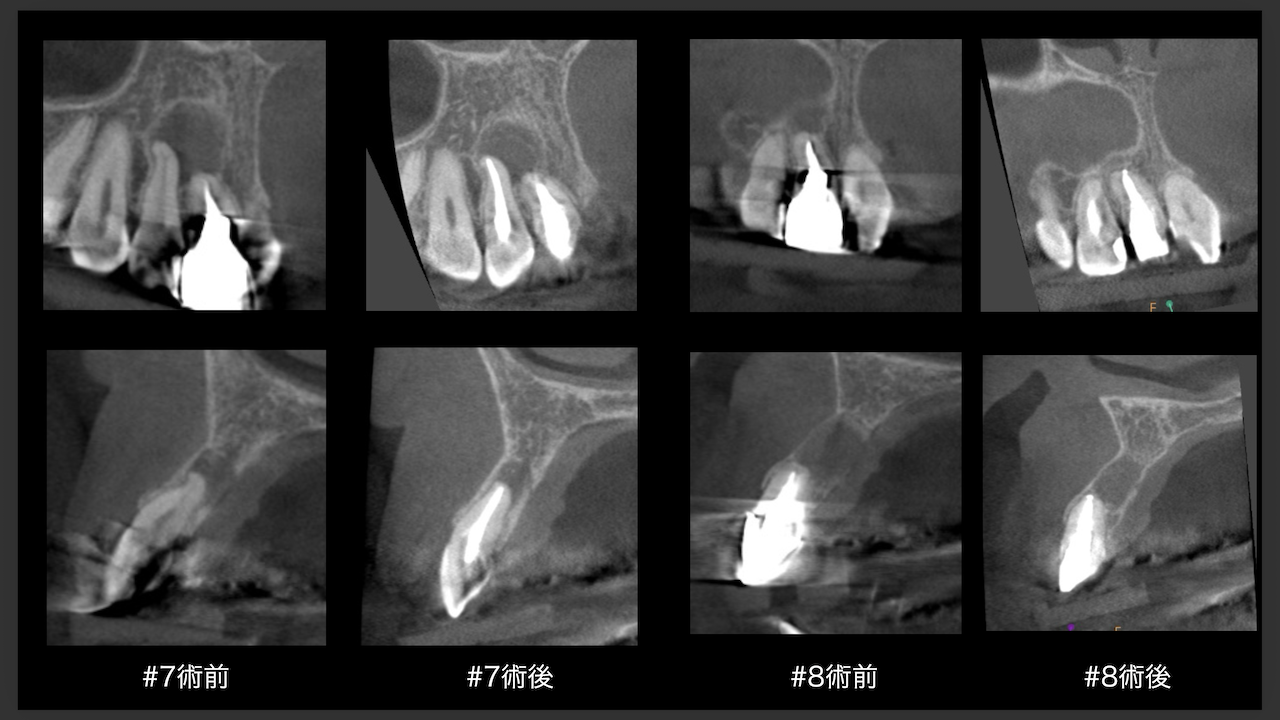

CBCTでは2本とも口蓋側の皮質骨が消失している。

その結果、

ここから4ヶ月が経過すると…

臨床症状も皮質骨も大きく治癒している。

1年後の予後が気になるところであるが、すごくよくマネージメントできているだろう。